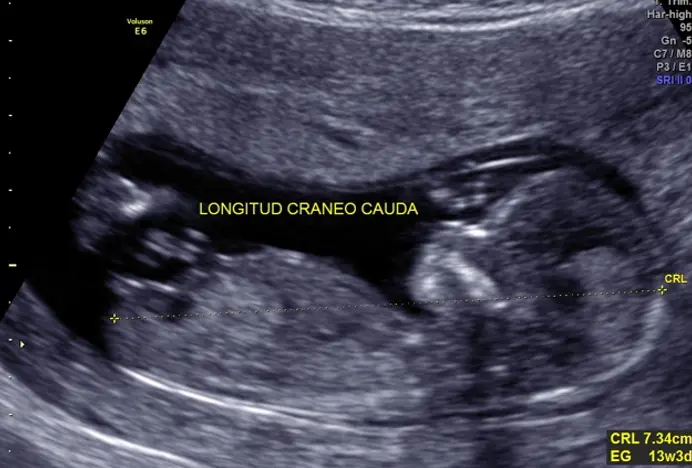

Ultrasonido de primer trimestre (entre las 11 y 13.6 semanas de embarazo)

Se conoce de varias maneras: estudio estructural de primer trimestre, genético de primer trimestre, combinado de primer trimestre, estudio 11-14.

Es el primer ultrasonido especializado que se deben realizar todas las pacientes embarazadas sin importar la edad, ya que en todas existen riesgos durante el embarazo.

En este estudio de primer trimestre se realiza una evaluación estructural detallada de bebé de cabeza a pies para descartar malformaciones mayores y revisar que todos los órganos vayan desarrollándose de manera normal, también se buscan cuatro marcadores en bebé que son llamados genéticos (translucencia nucal, hueso nasal, ductus venoso y flujo tricuspídeo), se sabe que en bebés sanos estos marcadores están presentes y deben ser normales, los bebés que los tienen alterados tienen mayor riesgo de alteraciones genéticas como síndrome de Down, como parte de este estudio se toma la presión del útero y en combinación con otros datos como peso, presión arterial del brazo, etc se puede calcular el riesgo de preeclampsia (presión alta al final del embarazo).

Los objetivos principales de este estudio son:

- Valorar viabilidad fetal (que el bebé tenga latido cardiaco).

- Calcular la edad precisa del embarazo.

- Evaluar el riesgo de alteraciones cromosómicas en el feto como Síndrome de Down.

- Evaluar riesgo de restricción de crecimiento fetal.

- Realizar una evaluación estructural temprana detalla para descartar malformaciones mayores.

- Identificar los tipos de embarazos gemelares (una o dos placentas).

- Evaluar el riesgo de presentar preeclampsia al final del embarazo (presión alta durante el embarazo).